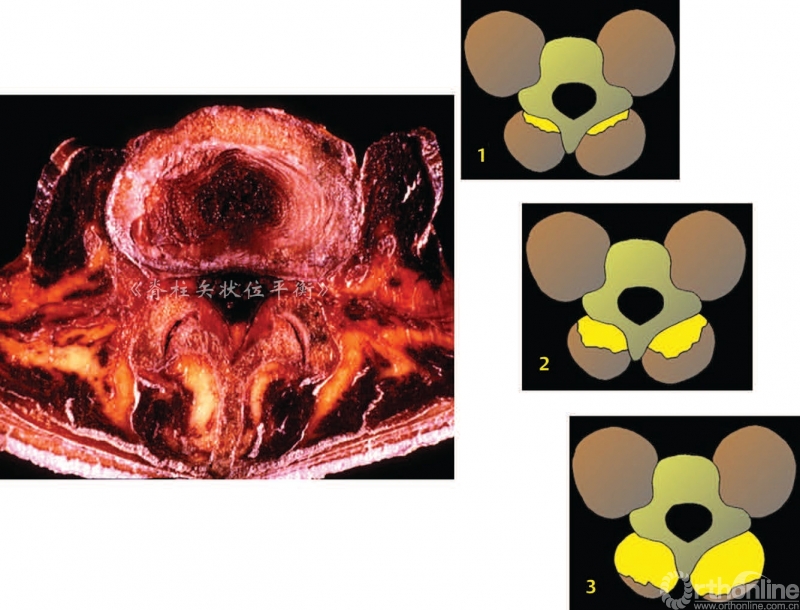

椎旁肌的退变以1型和2型肌肉纤维数量减少为特征。也可以观察到肌肉纤维,尤其是2型快速收缩纤维的萎缩。椎旁肌退变或者脂肪化过程是一种肌肉自然退变的现象,Hadar[2]对腰骶部的肌肉进行量化,提出了脊柱后方肌群脂肪变性的三个时期。

● Ⅰ期:受累肌肉横断面脂肪变面积50%

Ⅱ期:脂肪变面积达 50%

Ⅲ期:脂肪变面积50%图4

图4 肌肉脂肪退变的 Hadar分期

肌肉脂肪化是从深部向表面发展,多裂肌是第一个受累的肌肉,从远端向近端进展(从腰骶部到胸腰部Cruz[3]认为老龄化、腰椎前凸角度丢失和椎旁肌脂肪化程度三者之间呈正相关。

Fortin等[4]对多裂肌的磁共振成像进行了15年以上纵向研究,发现L5~S1多裂肌的萎缩程度显著高于L1~L2。肌肉脂肪化与体力活动(工作和运动)无关,但是与BMI具有相关性。

这种现象在退变性后凸的患者中尤为明显:我们发现在腰椎和胸腰段的受累肌肉严重的纤维化和脂肪化时,2型肌肉纤维几乎完全消失,可以见到虫蚀状、团块状、锯齿状红纤维组织。所有这些组织病理学的征象都可以在肌病中观察到[5](图5)。退变过程累及椎间盘、小关节、韧带和肌肉,导致了腰椎前凸角进行性的丢失。